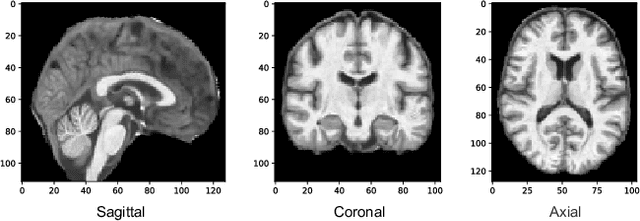

Abstract:Cross-modality translation between MRI and PET imaging is challenging due to the distinct mechanisms underlying these modalities. Blood-based biomarkers (BBBMs) are revolutionizing Alzheimer's disease (AD) detection by identifying patients and quantifying brain amyloid levels. However, the potential of BBBMs to enhance PET image synthesis remains unexplored. In this paper, we performed a thorough study on the effect of incorporating BBBM into deep generative models. By evaluating three widely used cross-modality translation models, we found that BBBMs integration consistently enhances the generative quality across all models. By visual inspection of the generated results, we observed that PET images generated by CycleGAN exhibit the best visual fidelity. Based on these findings, we propose Plasma-CycleGAN, a novel generative model based on CycleGAN, to synthesize PET images from MRI using BBBMs as conditions. This is the first approach to integrate BBBMs in conditional cross-modality translation between MRI and PET.

Abstract:Background: Beta-amyloid (A$\beta$) plaques and tau protein tangles in the brain are the defining 'A' and 'T' hallmarks of Alzheimer's disease (AD), and together with structural atrophy detectable on brain magnetic resonance imaging (MRI) scans as one of the neurodegenerative ('N') biomarkers comprise the ''ATN framework'' of AD. Current methods to detect A$\beta$/tau pathology include cerebrospinal fluid (CSF; invasive), positron emission tomography (PET; costly and not widely available), and blood-based biomarkers (BBBM; promising but mainly still in development). Objective: To develop a non-invasive and widely available structural MRI-based framework to quantitatively predict the amyloid and tau measurements. Methods: With MRI-based hippocampal multivariate morphometry statistics (MMS) features, we apply our Patch Analysis-based Surface Correntropy-induced Sparse coding and max-pooling (PASCS-MP) method combined with the ridge regression model to individual amyloid/tau measure prediction. Results: We evaluate our framework on amyloid PET/MRI and tau PET/MRI datasets from the Alzheimer's Disease Neuroimaging Initiative (ADNI). Each subject has one pair consisting of a PET image and MRI scan, collected at about the same time. Experimental results suggest that amyloid/tau measurements predicted with our PASCP-MP representations are closer to the real values than the measures derived from other approaches, such as hippocampal surface area, volume, and shape morphometry features based on spherical harmonics (SPHARM). Conclusion: The MMS-based PASCP-MP is an efficient tool that can bridge hippocampal atrophy with amyloid and tau pathology and thus help assess disease burden, progression, and treatment effects.

Abstract:Biomarker-assisted diagnosis and intervention in Alzheimer's disease (AD) may be the key to prevention breakthroughs. One of the hallmarks of AD is the accumulation of tau plaques in the human brain. However, current methods to detect tau pathology are either invasive (lumbar puncture) or quite costly and not widely available (Tau PET). In our previous work, structural MRI-based hippocampal multivariate morphometry statistics (MMS) showed superior performance as an effective neurodegenerative biomarker for preclinical AD and Patch Analysis-based Surface Correntropy-induced Sparse coding and max-pooling (PASCS-MP) has excellent ability to generate low-dimensional representations with strong statistical power for brain amyloid prediction. In this work, we apply this framework together with ridge regression models to predict Tau deposition in Braak12 and Braak34 brain regions separately. We evaluate our framework on 925 subjects from the Alzheimer's Disease Neuroimaging Initiative (ADNI). Each subject has one pair consisting of a PET image and MRI scan which were collected at about the same times. Experimental results suggest that the representations from our MMS and PASCS-MP have stronger predictive power and their predicted Braak12 and Braak34 are closer to the real values compared to the measures derived from other approaches such as hippocampal surface area and volume, and shape morphometry features based on spherical harmonics (SPHARM).

Abstract:Cognitive decline due to Alzheimer's disease (AD) is closely associated with brain structure alterations captured by structural magnetic resonance imaging (sMRI). It supports the validity to develop sMRI-based univariate neurodegeneration biomarkers (UNB). However, existing UNB work either fails to model large group variances or does not capture AD dementia (ADD) induced changes. We propose a novel low-rank and sparse subspace decomposition method capable of stably quantifying the morphological changes induced by ADD. Specifically, we propose a numerically efficient rank minimization mechanism to extract group common structure and impose regularization constraints to encode the original 3D morphometry connectivity. Further, we generate regions-of-interest (ROI) with group difference study between common subspaces of $A\beta+$ AD and $A\beta-$ cognitively unimpaired (CU) groups. A univariate morphometry index (UMI) is constructed from these ROIs by summarizing individual morphological characteristics weighted by normalized difference between $A\beta+$ AD and $A\beta-$ CU groups. We use hippocampal surface radial distance feature to compute the UMIs and validate our work in the Alzheimer's Disease Neuroimaging Initiative (ADNI) cohort. With hippocampal UMIs, the estimated minimum sample sizes needed to detect a 25$\%$ reduction in the mean annual change with 80$\%$ power and two-tailed $P=0.05$ are 116, 279 and 387 for the longitudinal $A\beta+$ AD, $A\beta+$ mild cognitive impairment (MCI) and $A\beta+$ CU groups, respectively. Additionally, for MCI patients, UMIs well correlate with hazard ratio of conversion to AD ($4.3$, $95\%$ CI=$2.3-8.2$) within 18 months. Our experimental results outperform traditional hippocampal volume measures and suggest the application of UMI as a potential UNB.